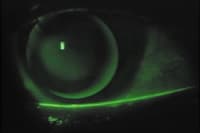

Figure 2. A15/6.60mm BC/8.50mm OAD. Excessive apical vaulting with adequate edge lift.

Once you select the initial diagnostic base curve, the ComfortKone fitting guide recommends that you choose an A value by subtracting the millimetric values of the flat and steep K readings and using the resultant number as the initial A value. However, for simplicity, we chose A values by consistently starting with an A value of A7 or A10. After allowing an appropriate settling time for the diagnostic lens (15 minutes, as the fitting guide recommended), we evaluated the fluorescein pattern with a Wrattan filter. We concentrated on base curve selection with the ComfortKone lens. If we found an unacceptable fluorescein pattern, we selected another diagnostic lens with a different base curve, but left the A value unchanged (Figures 2 and 3). Changing a specific, solitary parameter greatly simplified the fitting process, as base curve changes can result in subtle changes in the fluorescein pattern of the peripheral curves.